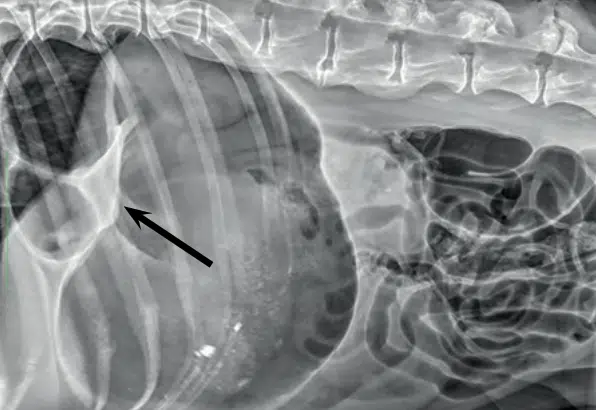

Radiography, specifically a right lateral radiograph of the abdomen, is required to determine a diagnosis. Thoracic radiographs are also helpful to determine the presence of aspiration pneumonia.

Typically, the pylorus is displaced dorsally and partly cranially, as most cases are attributed to 180 degree torsion. This is often accompanied by compartmentalization of the stomach, as is indicated by the arrow in the radiograph pictured (Humm & Barfield, 2017).

Orthogonal views should also be considered if there is any consideration of non-surgical treatment. If the pylorus is on the left of midline and dorsally displaced, this is pathognomonic for GDV. However, cases of 360 degree rotations may be challenging to diagnose even with radiography.